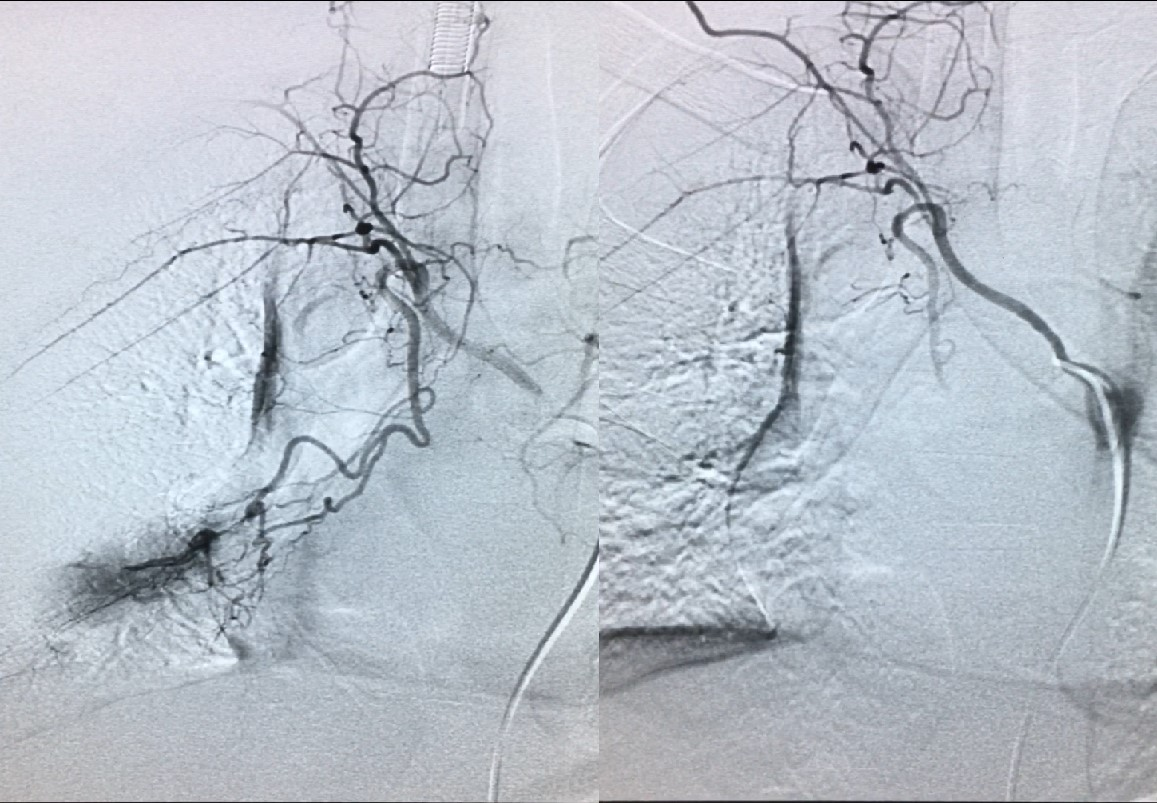

咯血

咯血是指喉及喉以下呼吸道或肺组织出血经口咯出的一种临床症状, 需要与呕血,口腔、咽、鼻出血等相鉴别, 咯血在儿童中少见,一旦出现便会大量咯血,需要密切关注,积极寻找病因。咯血病因有:特发性肺含铁血黄素沉着症、 肺结核、 支气管扩张症、 囊性纤维化、支气管异物、 肿瘤、血管畸形(儿童大咯血主要病因)。

咯血经导管动脉栓塞后造影畸形血管消失